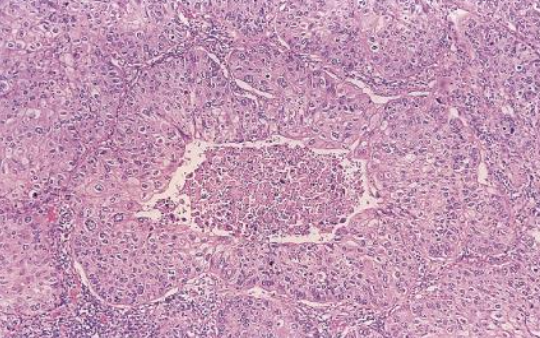

<p>Tumores carcinoides microscopicamente</p>

Tumores carcinoides microscopicamente

• Células organoides (nidos)

• Separados por estroma fibrovascular delicado

• Células regulares

• Núcleos redondos uniformes

Tumor carcinoide típico

<2 mitosis x 10 HPF, no necrosis